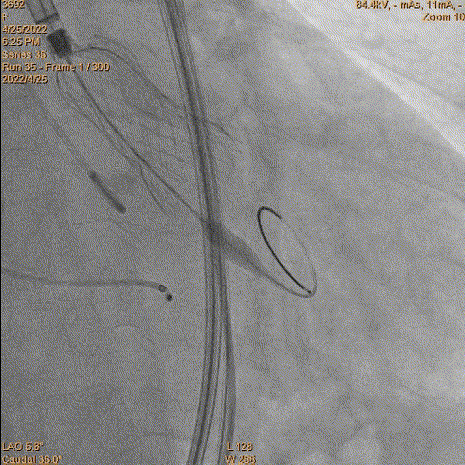

4、跨瓣:瓣膜跨瓣出现困难,计划使用圈套器。由于没有22F大鞘,内连鞘无法拆卸,选择左侧穿刺导入导管。右侧双导丝,送入Lunderquist,心室较大。扩张后,血压较稳定。经尝试无法退球囊,撤出系统。通过对侧使用抓捕器,将导丝全撤,导入AL1.0导管重新跨瓣。鉴于左侧入路有角度,使用泥鳅导丝带上导管,做圈套器。顺利抓住J型导丝,抓捕器顺利抓捕瓣膜过瓣。

重新过瓣

瓣膜过瓣